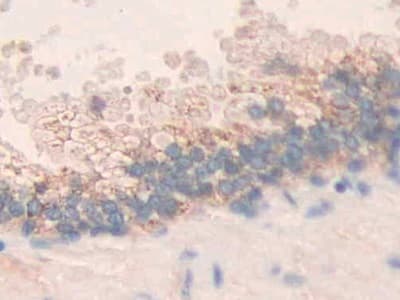

Rabbit Polyclonal MMP24 antibody. Suitable for WB, IHC-P and reacts with Rat, Human samples. Immunogen corresponding to Recombinant Fragment Protein within Human Matrix metalloproteinase-24 aa 400 to C-terminus.

Applications IHC-P, WB

Species Reactivity Human, Rat